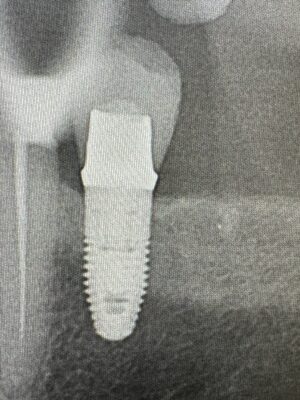

Hi, can someone please help me identify this implant please? Patient reports that she had the implant placed around 2007. Thank you!

Possible Implant Direct, or replace implant from Nobel. I would also recommend sending that information to your lab that sees lots and lots of different implants and they also could probably give you an idea what it is. I also find the website whatimplantisthat.com can be helpful as well